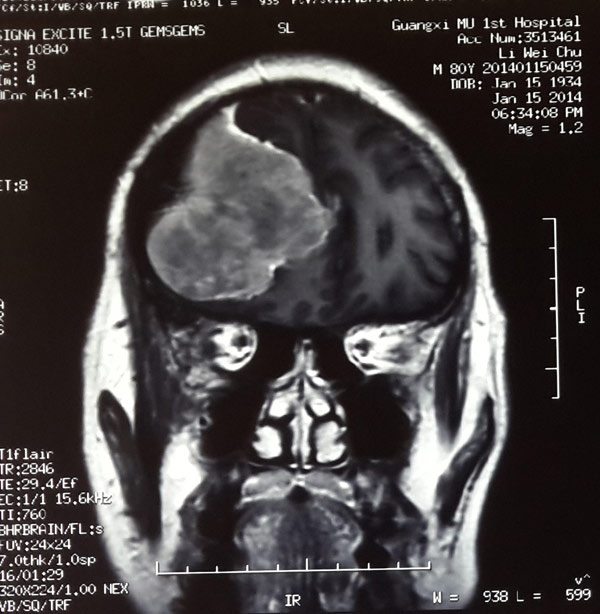

日前我院神经外科成功为一80岁高龄脑瘤患者实施了开颅肿瘤切除术,切除了一个5.6cm×6.3cm×5.7cm的巨大脑膜瘤,并保持了老人术后头颅外观形态正常,使其原本因肿瘤压迫脑组织导致无力的左侧肢体得以自由活动。

经过确诊,李大爷的病是由右侧额区凸面脑膜瘤引起的。正是这个肿瘤压迫了神经才造成老人左肢无力。但鉴于他年事已高,医生认为手术风险极大,家属在医生推荐下来到我院神经外科求救。

头颅CT显示,李大爷颅内肿瘤已经长至鸭蛋大小,立即手术是挽救老人生命的唯一办法。

术前可见巨大脑膜瘤